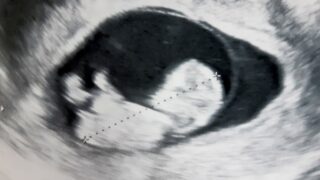

診察室で医師の説明を聞いた後、恵美さんと夫はふたりとも「ダウン症が分かったら産むことを断念したい」と感じ、医師にそう伝えた。夫婦で同じ思いだった――この時までは。

恵美さんと夫の感じ方が違うものになったのは、絨毛検査の結果が「陽性」と出て、はっきりと赤ちゃんがダウン症であるとわかった時だった。中絶という現実をいよいよ喉元に突きつけられると、恵美さんは、中絶に強い抵抗感を抱いた。 夫婦は激しい口論になった。

「私は、どうやって日一日と大きくなっていく、この赤ちゃんと別れられるのかわからないのに夫は一歩も退かず、絶対に育てられないと言い続けました。それなら、と私は『では、養子に出そう』と言ったのですが、それも『それは誰も幸せにしない選択だ』と言うのです」